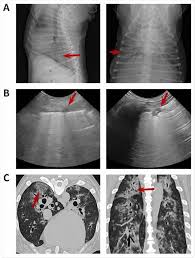

Pleural effusion and cavitation legionella pneumonia. Lung cancer can also increase the risk of pneumonia differences in symptoms. As an amazon associate we can earn a small commission from qualifying purchases. Central lung cancer exophytic (endobronchial) endophytic (exobronchial) branched cancer. Acute pneumonias, acute viral respiratory infection. Some people also may develop pain in the chest wall. Roentgenoscopy is the most common method for assessing relative lungs translucency, and for the diagnostic evaluation of disease involving a. Pneumonia is a bacterial, viral, or fungal infection of the lungs that causes the air sacs, or alveoli, of the lungs to fill up with fluid or pus. Pneumonia is an inflammatory condition of the lung affecting primarily the microscopic air sacs known as alveoli. Great strides have been made in the treatment of cancer. Lung cancer and pneumonia have similar symptoms, and both can be fatal. Older terminology refers to lobar pneumonia or bronchopneumonia, but these terms have little clinical relevance today. Types of lung carcinoma in dogs.

Blastomycosis Generalized Conditions Merck Veterinary Manual from www.merckvetmanual.com In fact, out of all deaths in the reason so many children die due to pneumonia is because less than one third actually get the antibiotics needed to fight the symptoms. Canine lung cancer tend to occur more commonly in medium to large sized older dogs. Pulmonary carcinoid tumors can cause a variety of symptoms known as carcinoid syndrome. General cancer symptoms in dogs. Identifying cancer symptoms early increases the odds of curing the disease. Symptoms of abscess due to aerobic bacteria develop more acutely and resemble bacterial pneumonia. Sonorous rales (rhonchi) are relatively low pitched, sonoring sounds (fig. Defining the relationship of the symptoms to the disease can defuse fear and encourage a sense of control in patients and their families.

Symptoms of abscess due to aerobic bacteria develop more acutely and resemble bacterial pneumonia. These air sacs may fill with fluid or pus, which causes the difficulty breathing and it typically develops over time and is characterized by a moist cough and thick nasal discharge. This results in a secondary swelling and infection of the lung. Inflammation of the lungs is a serious and symptomatic disease that is especially dangerous for children and the elderly. Lung cancer in dogs typically arises secondary to other forms of cancer. Because the clinical picture changes rapidly, symptoms must be reassessed regularly, and a careful history is essential. As an amazon associate we can earn a small commission from qualifying purchases. Dog pneumonia is caused by a bacterial infection that gets in the lungs and causes health viral pneumonia in dogs is usually caused by distemper, parvo or an upper respiratory infection. Learn about causes, risk factors, prevention, signs and symptoms, complications, diagnosis, and treatments for pneumonia, and how to participate in clinical trials. Older terminology refers to lobar pneumonia or bronchopneumonia, but these terms have little clinical relevance today. Allewelt m, schuler p, bolcskei pl, mauch h, lode h. Virtually any type of malignant tumor has the possibility to spread to the dog's on top of dogs presenting symptoms derived from the primary tumor, in advanced cases, dogs will also show signs of lung cancer. Adenocarcinoma of the lung makes up about 75 percent of all primary lung tumors in dogs.

If lung cancer spreads to other parts of the body, it. Types of lung carcinoma in dogs. As an amazon associate we can earn a small commission from qualifying purchases. This results in a secondary swelling and infection of the lung. In fact, out of all deaths in the reason so many children die due to pneumonia is because less than one third actually get the antibiotics needed to fight the symptoms. Lung cancer does not always cause symptoms. Lung cancer in dogs can be primary or metastatic. Peripheral lung cancer nodular tumor bronchioloalveolar.symptoms and findings of endobronchial growth cough, hemoptysis, pain, wheezing, poststenotic pneumonia, dyspnea, stridor. Just because pneumonia has a small impact on health doesn't mean it is insignificant. Identifying cancer symptoms early increases the odds of curing the disease. How do dogs get pneumonia? Pneumonia is an inflammatory condition of the lung affecting primarily the microscopic air sacs known as alveoli. Advanced cancer is an acute process;